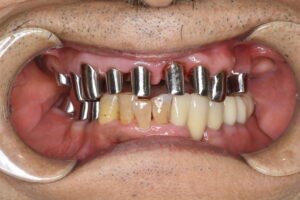

ケース2:上下に多くの問題があった70代後半男性

この方は虫歯や歯周病で残存歯が少なく、グラグラの歯が多い状態でした。最初は保険のクラスプ義歯を入れていたものの安定せず、硬いものを噛めないため外していることが多かったそうです。外見を重視してナイロン義歯を試されましたが、期待したような咬合回復は得られず、全体の再治療を希望して来院されました。

まず全顎の虫歯と歯周病の治療を行い、上顎は残存歯すべてに内冠をかぶせて連結し、全体を支えるテレスコープ義歯を製作しました。装着後は「入れ歯」というよりは取り外し可能な長いブリッジの感覚で、違和感がほとんどないとのことです。

このケースは「残った歯をチーム化して守る」発想が有効であった例です。